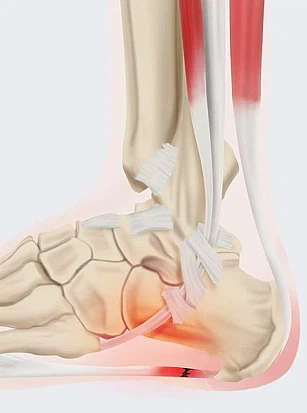

족저근막염은 쉽게 말해 발바닥 근육을 덮고 있는 막에 생긴 염증을 의미합니다. 족저근막은 발뒤꿈치뼈부터 발끝까지 이어지는 두껍고 강한 섬유로 발의 아치를 지탱해 발밑에 전달해지는 충격을 흡수하고 보행 시 발의 기둥이 되는 부분입니다.

족저근막에 염증이 발생하는 이유은 단단한 신발을 자주 신던지 발에 과도한 몸무게가 몰리기 때문입니다. 근막이 장기적으로 자극되면 염증이 생기게 됩니다. 대부분 하이힐, 쿠션이 없는 신발을 많이 신는 젊은 여성들한테 곧잘 발생하는 족저근막염은 발의 무리한 이용으로 말미암아 유발하는 족부질환으로 발생할 때 심각한 진통을 야기해 일상에 많은 지장을 주곤 합니다.

또 평시 활동을 잘 하지 않은 경우, 평발인 경우이거나 반대로, 발바닥이 너무 오목한 경우에도 족저근막염이 쉽게 생길 수 있습니다. 중장년 층에서는 노화로 인해 발에 지방이 감소하면 발바닥이 받는 충격이 더 커져서 족저 근막염 발병률도 높아지게 됩니다.